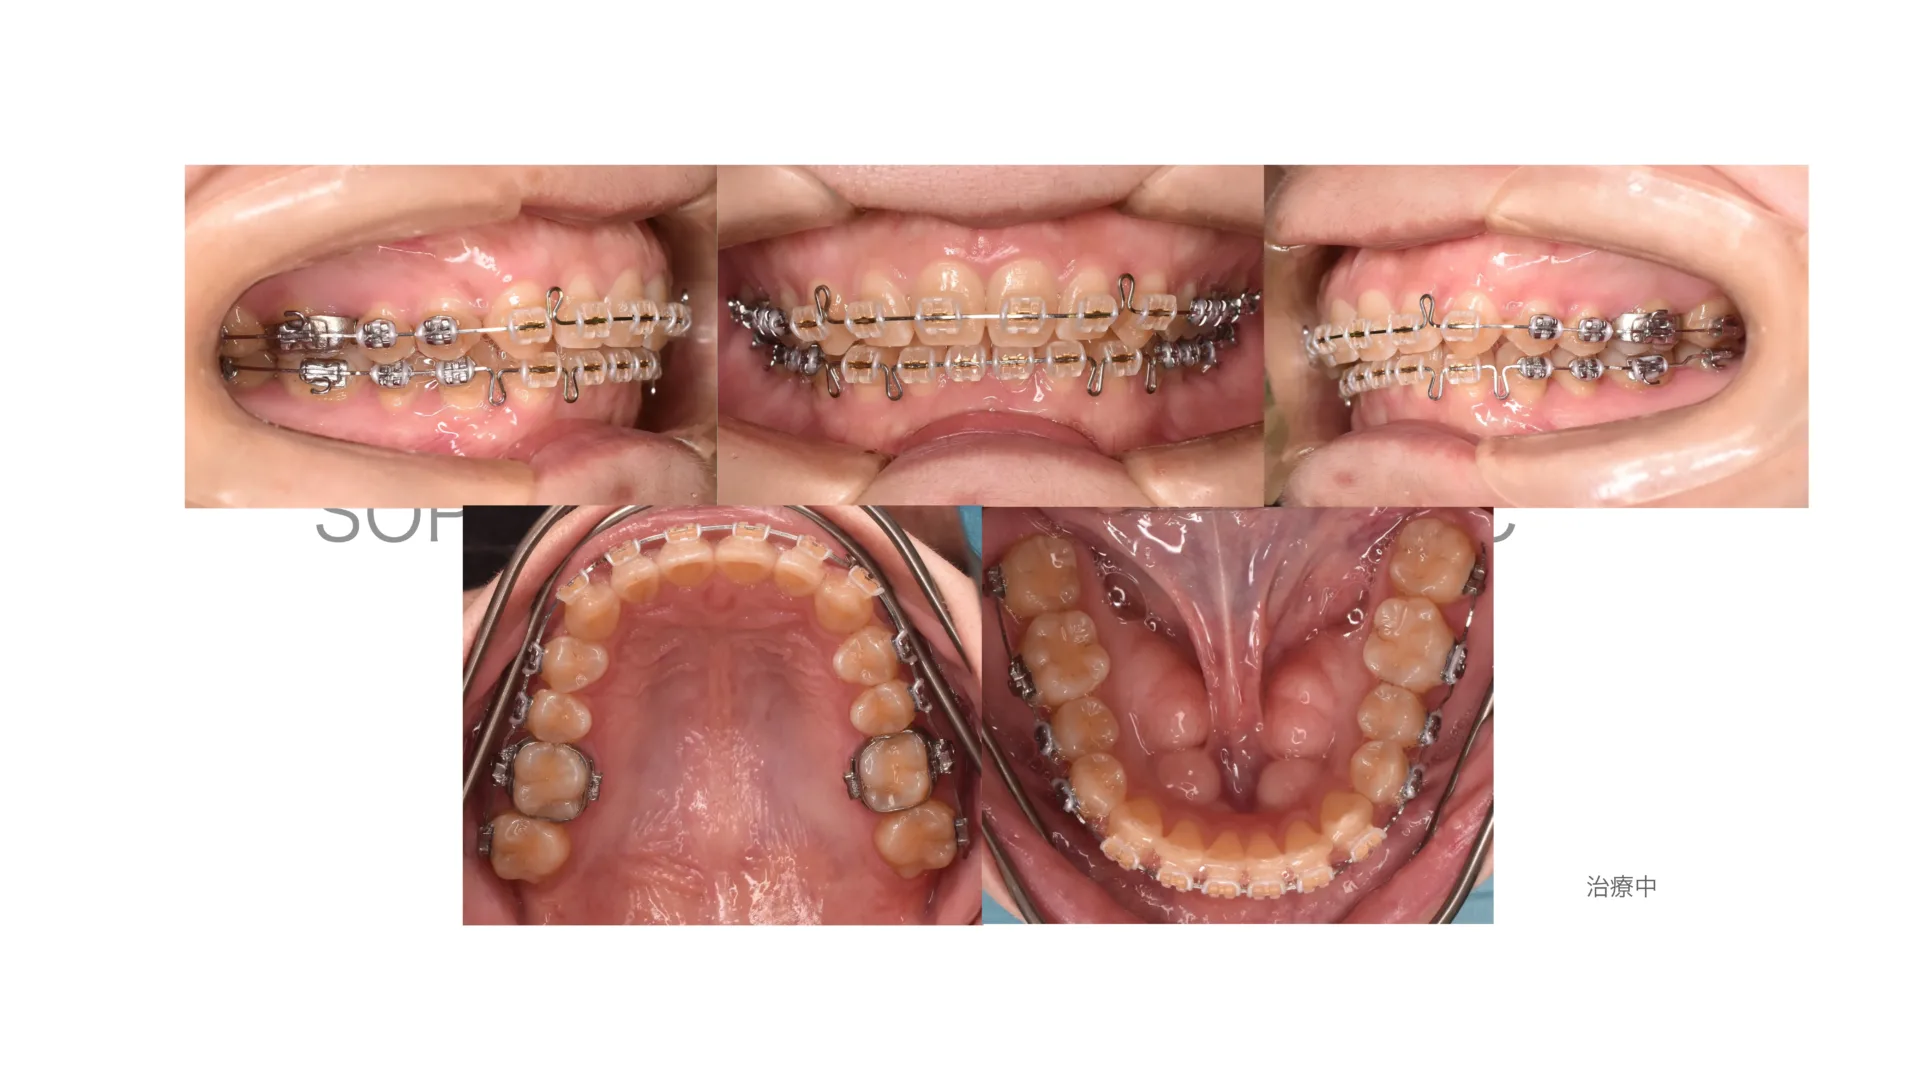

開咬症例 非抜歯 唇側